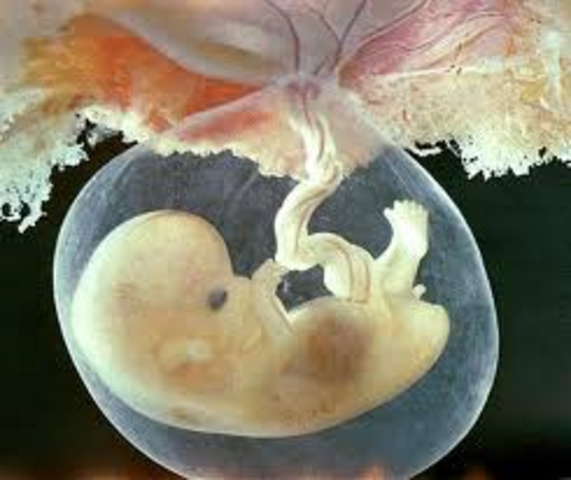

• 11 weeks pregnant

11 weeks pregnant

Your baby, just over 1 1/2 inches long and about the size of a fig, is now almost fully formed.She's already busy kicking and stretching, and her tiny movements are so effortless they look like water ballet. Her hands will soon open and close into fists, tiny tooth buds are beginning to appear under her gums, and some of her bones are beginning to harden.